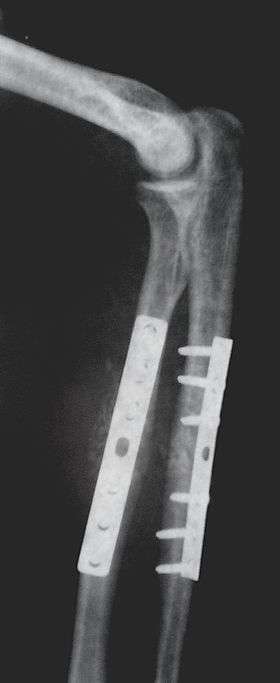

Closed Reduction Internal Fixation

Closed Reduction Internal Fixation (CRIF) is reduction without any open surgery, followed by internal fixation. It appears to be an acceptable alternative in unstable distressed or hyperfalotated [need reference, no results on the web for "falotated"] lateral condylar fractures of the humerus in children, but if fracture displacement after closed reduction exceeds 2 mm, open reduction and internal fixation is recommended.[3] Various techniques of minimally invasive surgery for internal fixation of bones have been reported. The treatment of fractures of the distal third of the tibia has evolved with the development of improved imaging and surgical techniques.[4]